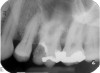

Excellent diagnosis essentially begins with two fundamental components: a doctor willing to listen to the patient’s chief complaint, and proper diagnostic tools. Among the most important tools are a precise periapical radiograph (PA) and bitewing (BW). Although a PA is often enough to provide an accurate portrayal of the patient’s condition, sometimes it alone does not suffice. Figure 1, Figure 2, and Figure 3 demonstrate a case that illustrates this point clearly. Despite two acceptable PAs (Figure 1 and Figure 2), it is difficult to assess the source of the patient’s pain to temperature. However, the BW radiograph Figure 3 provides significantly more clarity than either of the two PAs. The BW depicts localized bone loss (around tooth No. 2), a pulp stone (No. 2), a flat occlusion, numerous calcified canals, multiple restorations in tooth No. 30, and gross decay especially on tooth No. 3, which is the source of the patient’s pain to temperature. In this instance these images depict how much more useful a BW can be than just a conventional PA.

Fig 3. BW of the same upper right area as shown in Figure 1 and Figure 2, depicting gross decay not visualized on prior PAs.

Figure 3